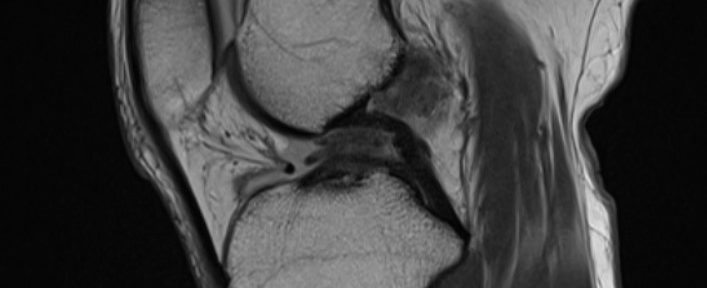

受傷後、他の接骨院にて電気治療等の治療を受けた。11月21日に整形外科を受診し、レントゲン撮影を行うも骨折は無し。この時、関節穿刺にて関節液を抜いた。11月26日にMRI検査を行い、以下の診断を得た。

前十字靭帯断裂

断裂した断端が不明瞭(Iharaの分類Ⅳ)

12月3日より当院のオンライン治療を開始し、ナチュラリゼーションの運動療法を毎日3回、自宅で継続した。治療開始から4ヶ月後に2回目のMRI撮影を行った。尚、機能的装具は日常的に装着しなかった。

MRI画像から、断裂した前十字靭帯の断端同士の癒合は確認できなかった。末梢の前十字靭帯断端は後十字靭帯と癒合していた。この時点で、医師によるラックマンテストの評価は陰性であった。その後、関節可動域訓練や筋力トレーニングを行い、日常生活では全く問題を生じないレベルまで回復していた。同年7月からビーチボールを段階的に復帰した。プレー時に、過度に左に体を捻ると、膝に不安定性を感じていた為、テーピングとサポーターを装着し、プレーを行っていた。

12月9日、三回目のMRI撮影を行った。

3回目のMRI画像では、2回目と大きな変化はなく、変形治癒のまま形態は固定していると考えられる。